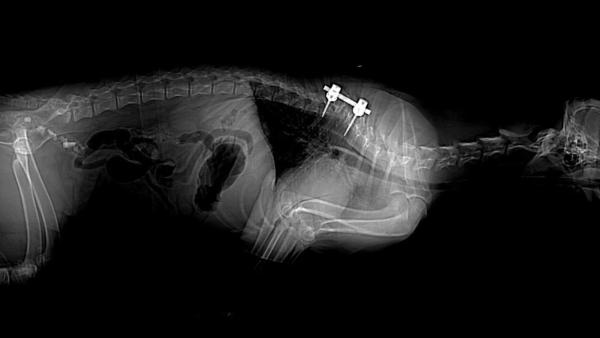

Thailand makes history with nation's first cat pacemaker surgery